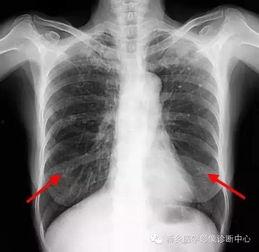

胸片检查是诊断肺部疾病的重要手段。通过观察肺部影像,医生可以初步判断患者是否患有肺炎、肺结核、肺癌等疾病。